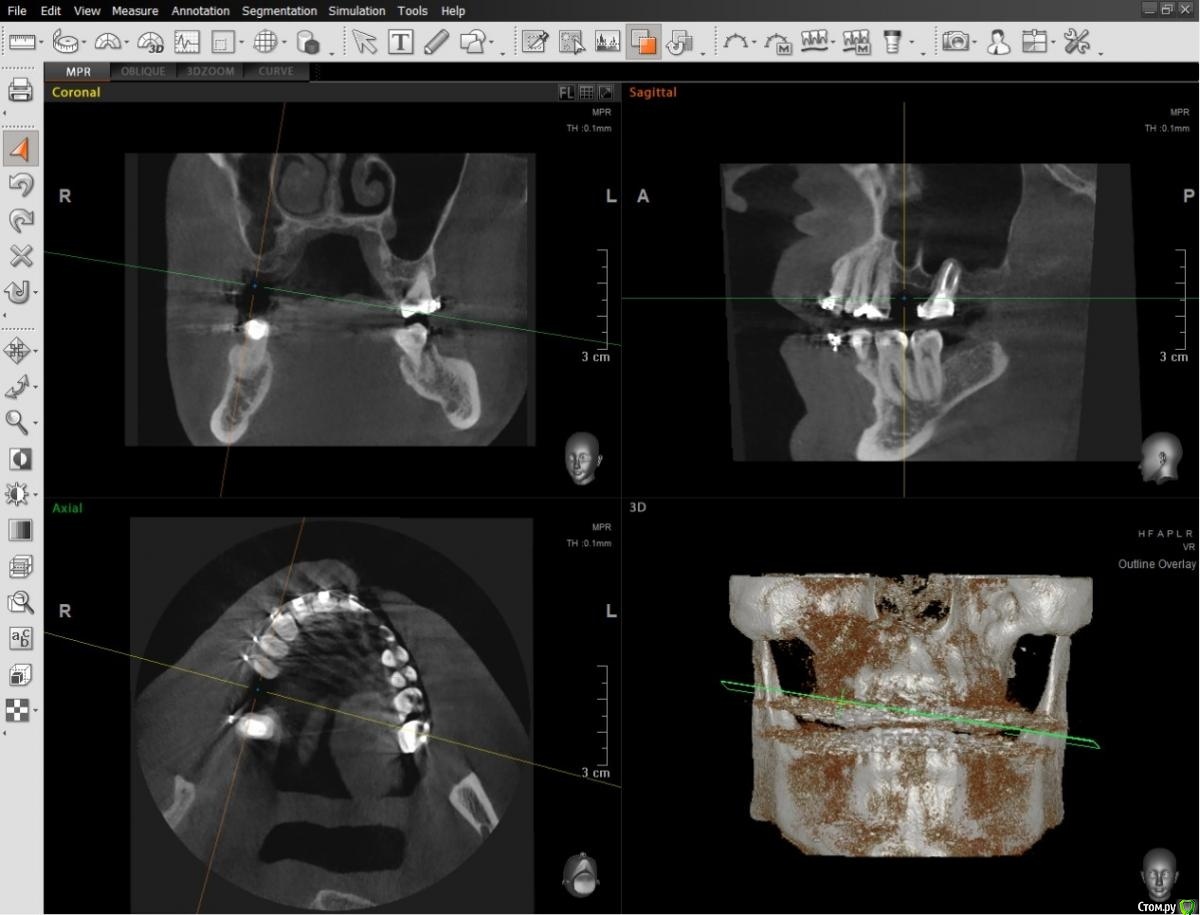

al7777 Опубликовано 10 января, 2021 Поделиться Опубликовано 10 января, 2021 Добрый день.У меня подходит к завершению лечение брекетами и нужно делать имплантацию верхней шестерки справа.Когда касался этого вопроса лет 5 назад, говорили, что нужен открытый синус-лифтинг. Проблема в септе, которая делит место для зуба надвое. Высота кости в этом месте около 4 мм, на снимке видно измерение.Сейчас 2 разных врача предложили сделать закрытый синус-лифтинг.Хотелось узнать мнение уважаемых специалистов с форума по этому поводу. Первый вариант - Установка короткого импланта большого диаметра (5х8 вроде) прямо под септой, синус-лифтинг будет "без применения костнозамещающего материала", имплант Корейский Implantium. Второй вариант от другого доктора- Установка импланта несколько под углом, так чтобы увеличить длину его контакта с костью и выйти с одной стороны от септы. От септы мембрану в пазухе не отслаивать, так как она при этом порвется, а синус-лифтинг сделать закрытым способом, с одной стороны от септы, там где выйдет имплант. Имплант корейский Осстем (можно и Штрауман поставить, но по деньгам сейчас не потяну), плюс пластика мягких тканей. Снимки прикладываю, единственное панорамные снимки сделаны перед установкой брекетов, не смог сейчас сделать панораму с КТ Пикассо. Ссылка на комментарий

al7777 Опубликовано 10 января, 2021 Автор Поделиться Опубликовано 10 января, 2021 Снимки с КТ актуальные, старые только панорамные снимки. Этого достаточно или нет? Ссылка на комментарий